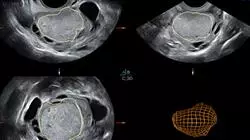

Com a participação de profissionais do mais alto nível de excelência, este Curso de especialização reúne todas as especialidades envolvidas na Adenomiose e no tratamento da Endometriose. Oferece uma preparação multidisciplinar única para adquirir o mais alto grau de especialização na doença.

Terá a oportunidade de aprender a utilizar e a interpretar as novas tecnologias e os testes genéticos mais recentes no diagnóstico precoce da Endometriose.

Este Curso de especialização foi concebido para ajudar os profissionais a assistir e tratar da melhor forma os pacientes que sofrem de Endometriose. Através da aprendizagem teórico-prático proporcionada por professores experientes, assegura-se a melhor qualificação e educação possível na área Adenomiose e Tratamento da Endometriose.

Através do conhecimento e da compreensão adquiridos, o aluno será capaz de ser independente na avaliação exaustiva da Endometriose, bem como na tomada de decisões sobre o seu curso evolutivo, tornando-se um especialista certificado em Endometriose.